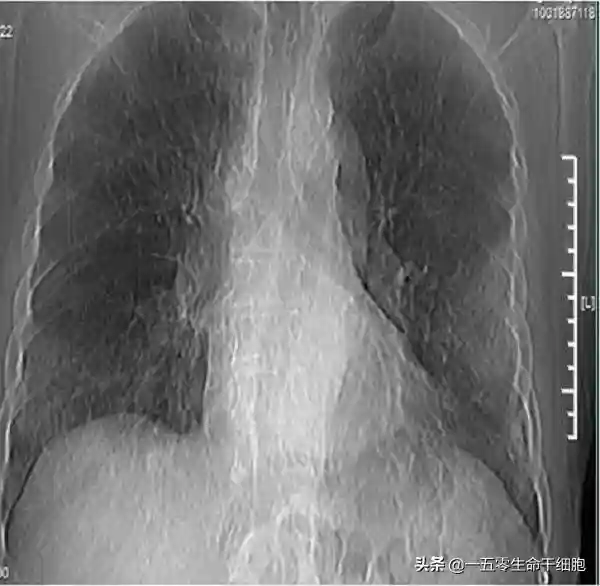

干细胞是一类具有自我更新复制和多向分化潜能的原始细胞群体,已通过小鼠等动物模型和大量临床前研究证实了全身性或气道内输入干细胞对多种肺部疾病(肺损伤、肺纤维化等)有效。

2020年1月27日,浙江省防治新型冠状病毒肺炎专家组成员黄建荣教授受记者采访时透露,发现干细胞对于禽流感患者的肺部感染,肺纤维化有比较好的效果,因此准备对新型冠状病毒重症的病人,应用这样的方法,目前这个项目已通过了医院的伦理委员会的讨论。